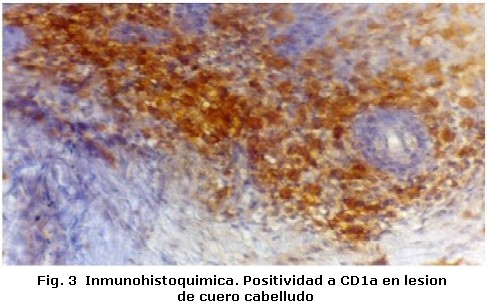

Un varón de tres años de edad con diagnostico de Histiocitosis de Células de Langerhans con afección ósea multifocal y otros sitios especiales fue referido al Servicio de Odontopediatría del Hospital Universitario de Maracaibo por el Servicio de Oncología Pediátrica del mismo Hospital, para valoración. El examen médico reveló, exoftalmos, palidez mucocutánea con pápulas eritematosas, lesiones hipercrómicas en miembros inferiores, dermatitis seborreica en cuero cabelludo, múltiples adenopatías cervicales y otitis supurativa recurrente. El informe de las pruebas de laboratorio indicó anemia y diabetes insípida. La biopsia de cuero cabelludo y el estudio inmunohistoquímico de la muestra tomada (Figura 1, 2 y 3) confirmaron el diagnóstico clínico, mientras que el examen de líquido cefalorraquídeo y médula ósea reportaron ausencia de infiltración. En las imágenes de resonancia magnética cráneo-facial, se evidenció realce anormal sugestivo de infiltración de huesos de base craneana y fosa anterior y media, mientras que la tomografía axial computarizada, reportó ausencia parcial de arco cigomático del lado derecho e imágenes osteolíticas en hueso temporal y pared orbitaria externa del mismo lado, acompañadas de lesiones similares en techo de orbita del lado izquierdo (Figura 4). Otros estudios, como tomografía de abdomen, pelvis y tórax, electroencefalograma, Rx de huesos largos, tórax óseo y columna, no revelaron hallazgos de interés. Durante la evaluación odontológica, la exploración extraoral evidenció exoftalmos y las lesiones de piel antes descritas; intraoralmente se registró la presencia de placa dental, gingivitis y hemorragia (Tabla 1), acompañada de movilidad dental, bolsas periodontales y recesión gingival (Figura 5) en la zona posterior izquierda de ambos maxilares (Tabla 2), además de caries dental y erupción prematura del 26. Radiograficamente se observaron lesiones osteolíticas, de bordes mal definidos, que medían aproximadamente entre 0,5 y 1,5 cm. de diámetro, localizadas en relación al 64, 65, 26, 74, 75, 85, también se observó agenesia de los gérmenes del 35 y 45 (Figura 6). Para el momento de la evaluación odontológica el paciente estaba recibiendo tratamiento con vasopresina y quimioterapia con vinblastina y prednisona. El manejo odontológico incluyo una fase inicial preventiva en la cual se instruyo a los representantes y al niño sobre hábitos de alimentación, higiene bucal y técnicas de cepillado y una fase quirúrgica llevada a cabo bajo anestesia general. Previa valoración sistémica y premedicación con antibioticoterapia se realizaron exodoncias del 65, 26, 74, 75 y curetaje de las lesiones. El resultado de la biopsia del tejido encontrado en los maxilares reportó un infiltrado inflamatorio severo, constituido por acumulo de linfocitos, histiocitos espumosos y células plasmáticas, mientras que el estudio inmunohistoquímico realizado con proteína S-100 y CD1a resultó negativo. Después de dos meses de seguimiento, el paciente cicatrizó favorablemente con persistencia en el 64 de recesión gingival, exposición de dos tercios de la raíz distal y movilidad leve. Radiograficamente se observan signos de osificación en las zonas intervenidas, sin embargo, es necesario seguir monitoreando al paciente para descartar la aparición de nuevas lesiones (Figura 7).

La Histiocitosis es una rara enfermedad cuyas manifestaciones clínicas son muy variadas; en el caso reportado, las características clínicas coinciden con algunas típicamente descritas en la literatura en relación a la edad, dermatitis seborreica, diabetes insípida, exoftalmos y lesiones óseas multifocales1-4. Este último tejido es uno de los más afectados1, nuestro paciente presentó lesiones en ambos maxilares y de forma bilateral en mandíbula, aunque en mayor grado del lado izquierdo. Desde el punto de vista clínico estas lesiones pueden semejar enfermedad periodontal y provocar movilidad dental2, la afectación ósea en nuestro paciente provocó erupción prematura del 26, recesión gingival y grado severo de movilidad dental; situación agravada por la presencia de irritantes locales. Un hallazgo que no hemos podido constatar con la literatura revisada, es la ausencia de los gérmenes del 35 y 45 sin relación con historia familiar, la cual podría catalogarse como agenesia, ya que de acuerdo a la secuencia y cronología dental, a los tres años edad deberían observarse signos de su formación7. Por otra parte, la ausencia bilateral de los gérmenes y la presencia de importantes lesiones osteolíticas solo en relación al 35, descarta la posibilidad de que las células infiltrantes hayan sido responsables de hallazgos similares en el lado contralateral donde la lesión era inferior a 0,5 cm. Sin embargo, es necesario descartar otros factores responsables de la agenesia dental antes de definir su etiología. El estudio inmunohistoquímico realizado a la lesiones intraorales no reveló positividad para S-100 y CD1a, a pesar de haberse encontrado positivos en la biopsia a inicial de cuero cabelludo. Estos marcadores además del CD207 han sido catalogados como específicos para la determinación de células de Langerhans; sin embargo se ha reportado hasta un 13% de resultados negativos para CD1a y un 7% para el CD2078. Los resultados obtenidos en la inmunohistoquímica de las lesiones maxilares, también podrían estar relacionados con los efectos producidos por la quimioterapia sobre las células infiltrantes. No obstante otros factores relacionados con la toma de la muestra no pueden descartarse como responsables de estos hallazgos. La decisión de seleccionar la cirugía, quimioterapia y/o radiación como tratamiento en la histiocitosis, dependen de la extensión de las lesiones, el grado de tejido involucrado y de la presentación unifocal o multifocal1,3. En este caso se decidió realizar exodoncias de los dientes con grado de movilidad severa y curetaje, con el fin no solo de tratar las lesiones maxilares sino de controlar el riesgo de infección. Se concluye que los maxilares al igual que los huesos del cráneo deben ser evaluados en pacientes con diagnóstico de Histiocitocis de Células de Langerhans, ya que estos pueden ser los únicos huesos afectados como sucedió en el caso estudiado. Por otra parte es importante resaltar que a pesar de la importancia de las pruebas inmunohistoquimicas en el diagnostico de esta enfermedad, su resultado siempre debe ser correlacionado con los hallazgos clínicos, radiográficos e histológicos encontrados en cada caso en particular.